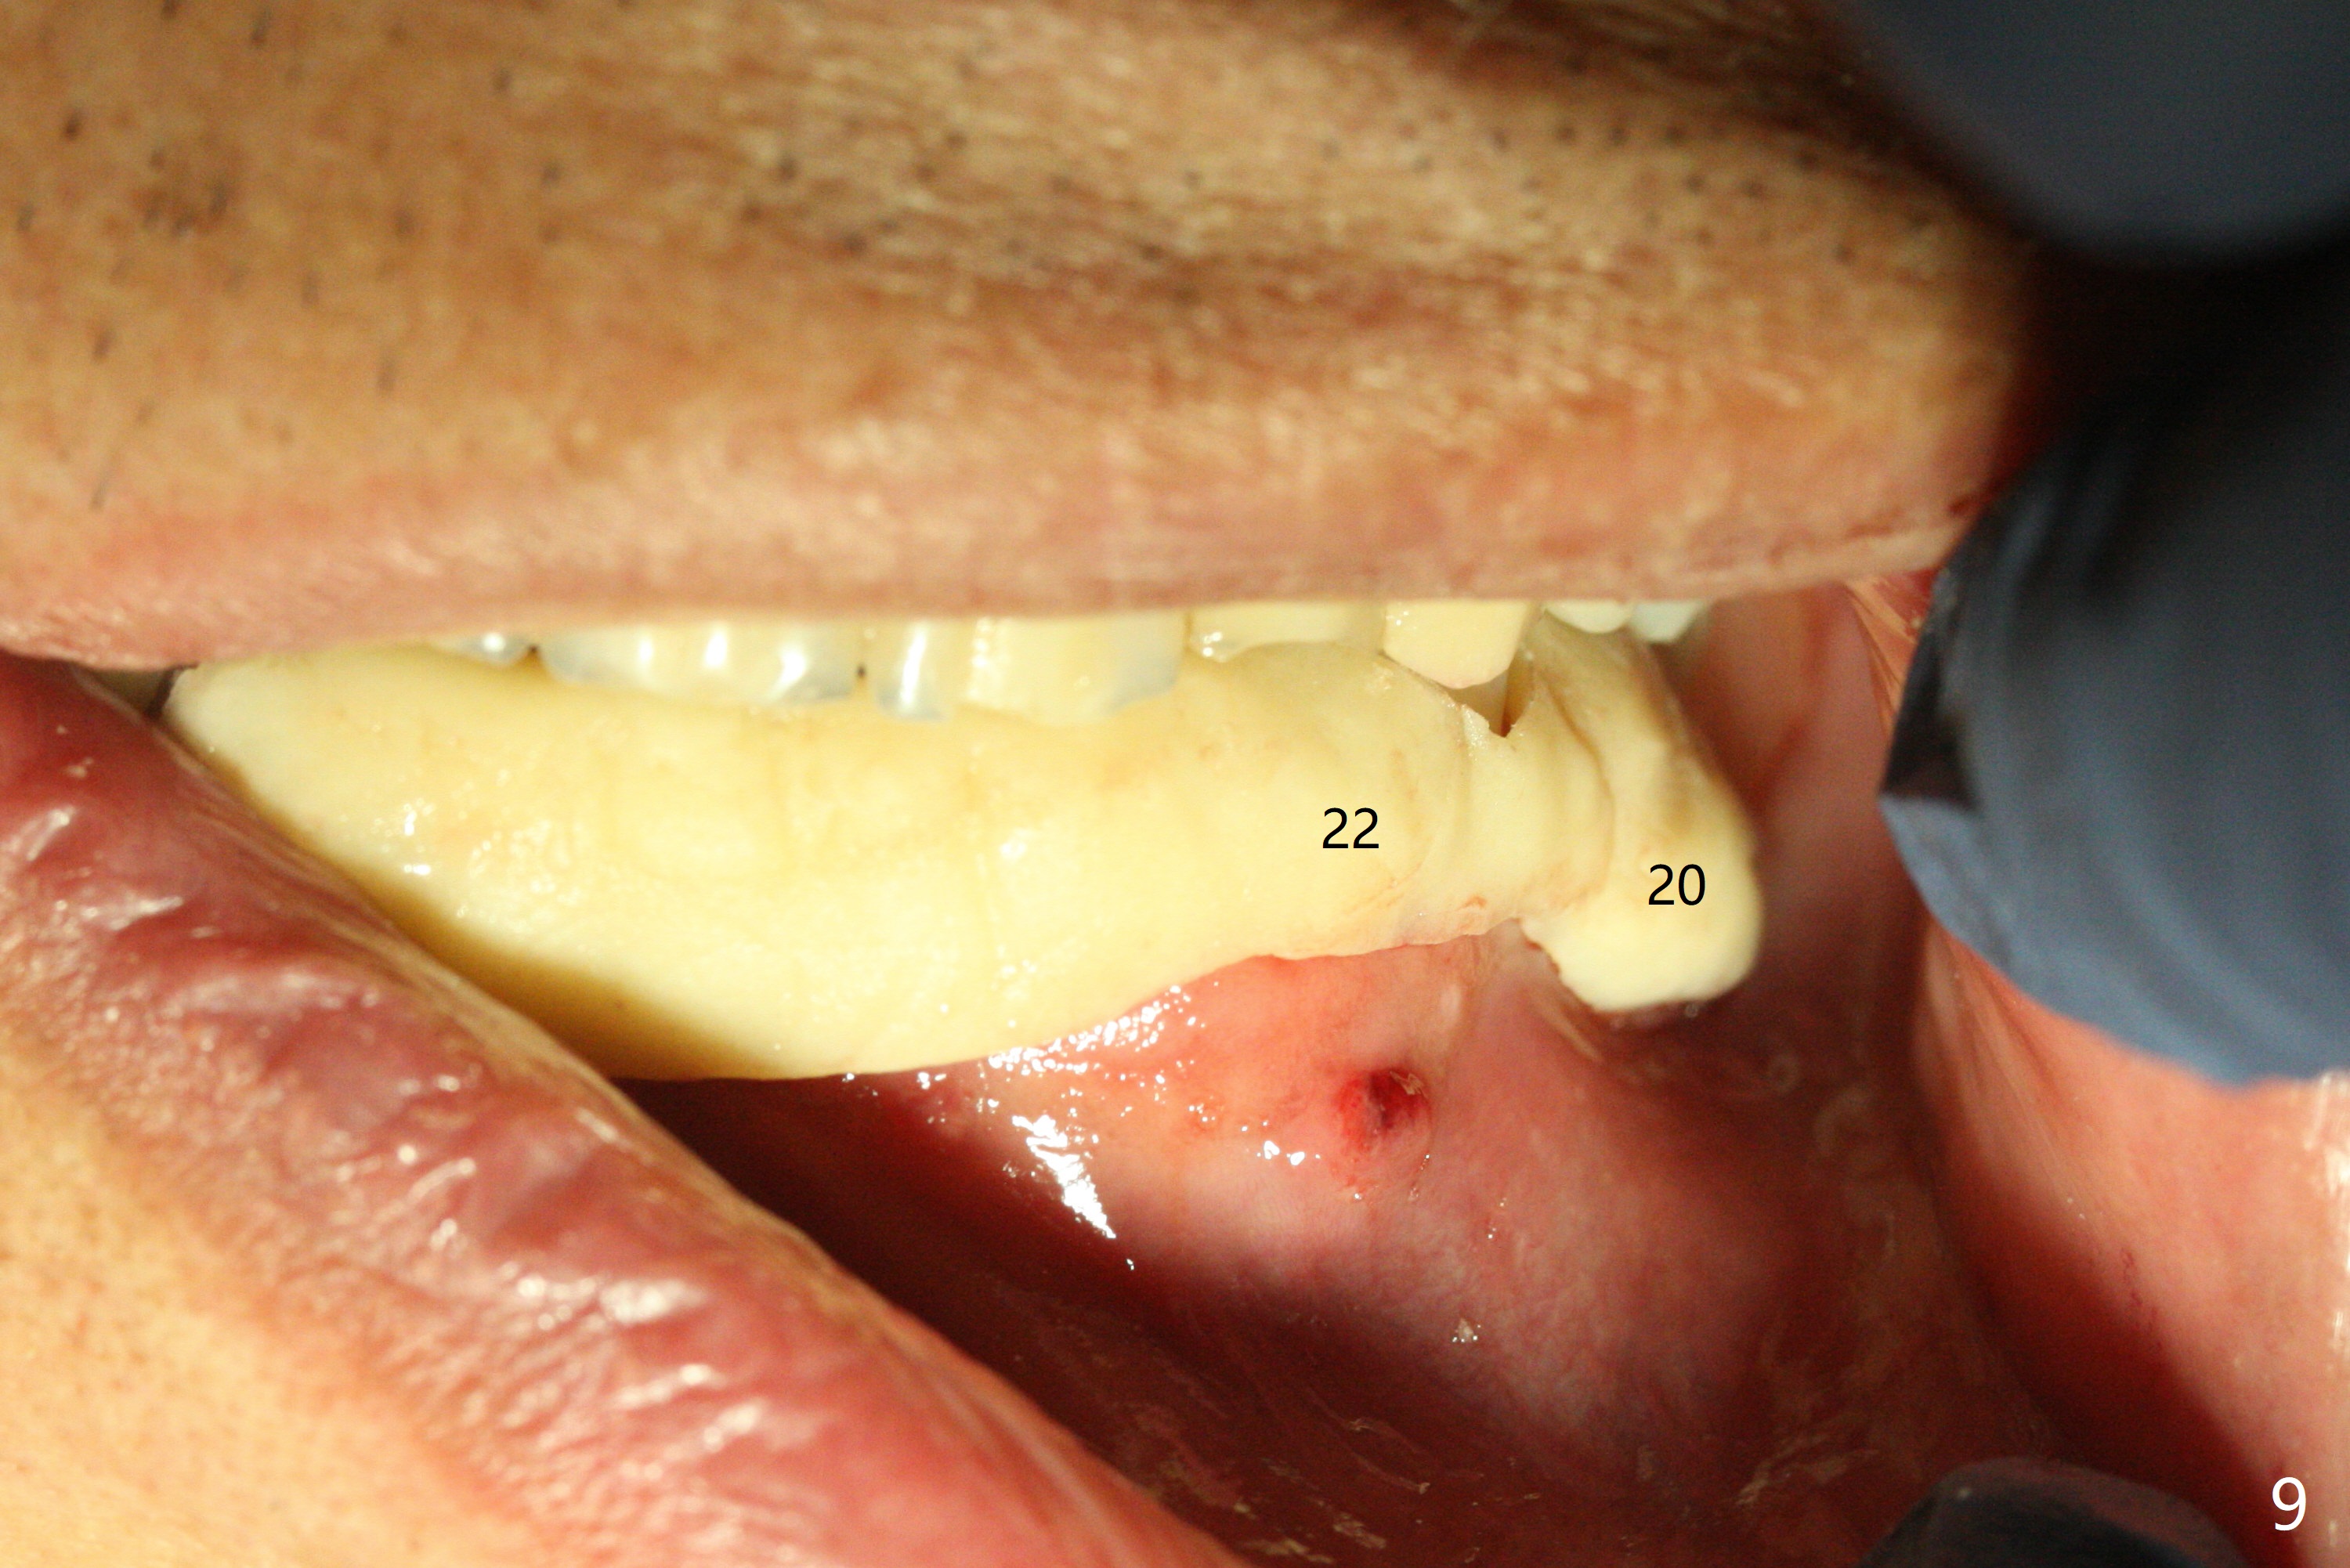

Three months post socket preservation (with buccal plate loss previously), a 3.5x11.5 mm implant is placed at #27 subcrestal (Fig.1). When implants are placed at #22 and 20 (Fig.2,4), threads are exposed buccal (B). Mixture of autogenous bone and allograft is placed to cover the exposed threads (Fig.3,5) following deep placement at #20. For safety, the implant at #20 is buried. Pain control at #18 is poor when initial osteotomy is being established (Fig.6 *), as related to severe infection. Repeated block anesthesia allows to finish implant placement with primary stability; a 3.5x2 mm ball abutment is placed (Fig.7). With placement of 2 other ball abutments at #27 and 22 (Fig.3), the lower existing RPD is converted to a removable provisional (Fig.8). With addition of acrylic, the socket of #20 is covered (Fig.9). There is no apparent bone #20 distal 3 months postop (Fig.10,11 <). Re-graft is needed? The implant at #21 appears immediately subgingival 5 months postop (Fig.12 *). The distobuccal threads are exposed (Fig.13). After decortication, allograft is placed, followed by 6-month membrane. In fact, a shorter and smaller implant should be placed instead. The patient has to wear the RPD for mastication. It would be more painful without it. Later the tissue surface of the RPD is trimmed.